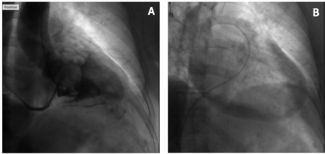

A 78-year-old woman admitted for anterior non-ST elevated myocardial infarction underwent coronary angiography, which showed a critical stenosis of the proximal and distal left anterior descending artery (LAD). After predilation, the distal...